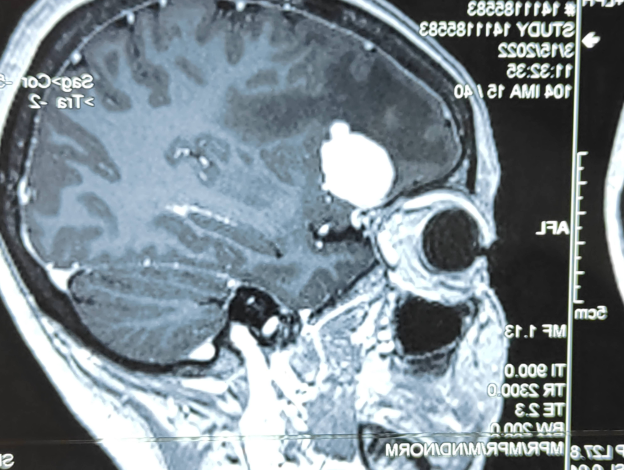

入院后,戴姐做了一系列檢查。確診為顱內占位性病與左側面神經麻痹儀。器屏幕中,只見戴姐的腦膜里,赫然橫亙著一塊像雞蛋般大的“攔路石”一個腫瘤,唐運林教授結合多年的診療經驗,告知她腫瘤及感染侵犯的范圍十分巨大,上至額竇、顱底,下至軟腭、牙齒;腫瘤引起的缺損在顏面部還超過了面中線,在這個范圍內存在大量十分重要的血管、神經及器官,術中稍有不慎,就會引起不可挽回損害,甚至有很大的生命危險。

戴姐的顱內占位性病就是俗稱的腦膜血管球瘤,是血管性腫瘤,呈球形或結節(jié)性生長,由于腫瘤組織供血豐富,局部解剖復雜,給手術切除增加了難度。在門診常常對該疾病的漏診與誤診,導致多數患者長期得不到正確治療,面孔恐怖,痛苦異常,嚴重影響工作和生活。